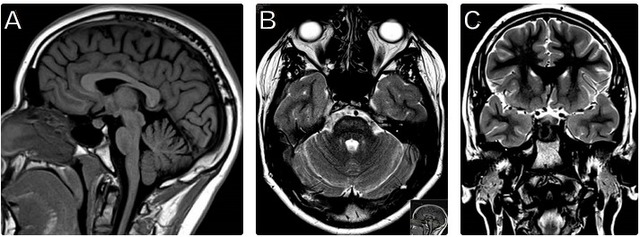

13 岁男性患者,主因进行性双侧视力丧失和感觉神经性听力丧失来诊。既往有 1 型糖尿病,控制不佳。头颅影像学检查结果见下图。

图 1 患者头颅磁共振检查结果。(A)矢状位 T1 像显示神经垂体 T1 高信号消失,视神经颅内段萎缩。(B)轴位 T2 像显示脑桥轻度萎缩且信号增高。(C)冠状位 T2 像显示双侧视神经萎缩

1. 典型的头颅 MRI 表现:

1)垂体后叶 T1 正常高信号消失;

2)双侧眶内和颅内视神经萎缩;

3)脑桥 T2 高信号;

4)进行性脑干、小脑萎缩;后期出现全脑萎缩。